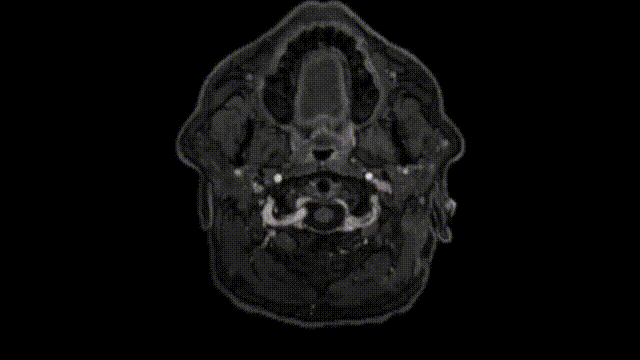

Froelich教授解读扩大翼点入路与中窝钻孔和内镜辅助技术:

入路选择要点

Froelich教授视频截图

手术体位:仰卧位,右肩抬高。头部倾斜并转动45度,稍微伸展。

手术切口:一开始手术的右侧额颞皮肤切口